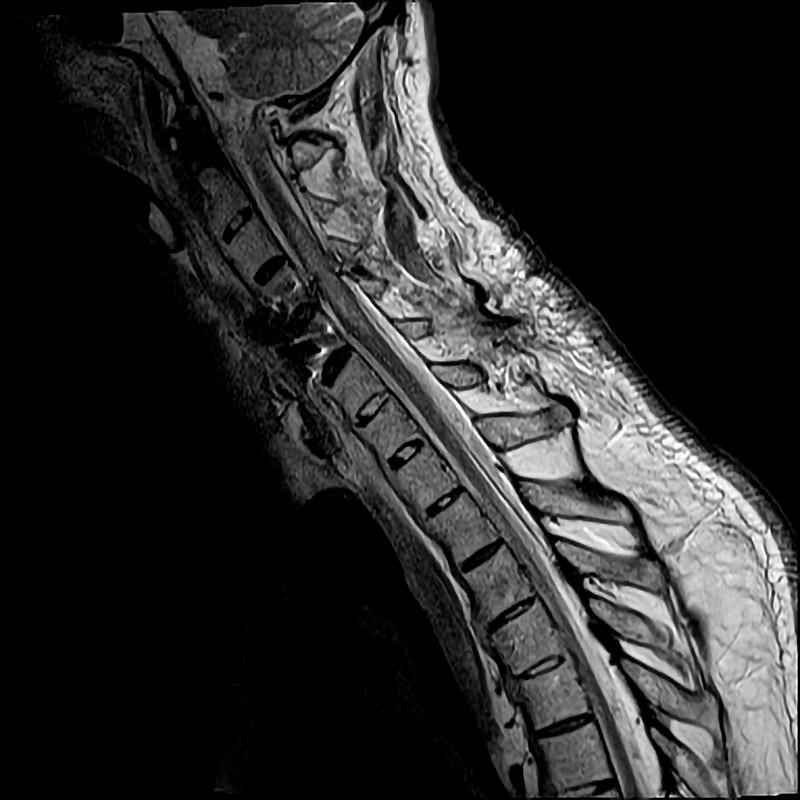

A man in his seventies with ankylosing spondylitis, type 2 diabetes and coronary artery disease was admitted to the surgical department of a local hospital after a fall on the stairs. Upon arrival in Acute Admissions, he was conscious and oriented but lacked motor responses in his upper and lower extremities. His airway was unobstructed, heart rate was regular and normal, and blood pressure was 80/60 mm Hg. CT of the head, neck, thorax, abdomen and pelvis in line with the trauma protocol showed a cervical fracture at level C4–C5. After the CT scan, the patient became unresponsive. Blood gas measurement showed respiratory acidosis, and hypoventilation was suspected. The patient was immediately intubated. Supplementary CT of the head with angiography showed no sign of traumatic bleeding, but rather cessation of circulation in both vertebral arteries with retrograde filling of the posterior cerebral artery, consistent with dislocation of the vertebral arteries as a consequence of the cervical fracture. The man was transferred to the neurosurgical department of the nearest regional hospital where he underwent emergency surgery with repositioning of the cervical fracture and osteosynthesis. Brain MRI after surgery showed restoration of circulation in the vertebral arteries without cerebral infarction. Spinal cord MRI showed spinal cord oedema at level C2–C5 consistent with a spinal cord injury (Figure 1).

Figure 1 MRI of the cervical spine after surgical fixation at the C4–C5 level. Centromedullary injury can be seen at levels…

Figure 1 MRI of the cervical spine after surgical fixation at the C4–C5 level. Centromedullary injury can be seen at levels C3–C6.